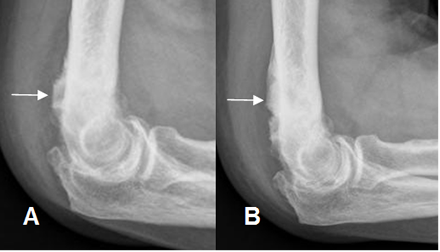

Fig 78. Osteocondroma.

A: Rx lateral y B: Rx AP. Osteocondromatosis múltiple en diferentes pacientes .